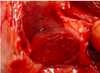

Identify

Bile Imbibition

How does bile imbibition occcur?

Bile in the gallbladder starts to penetrate the wall and stains the adjacent tissue yellowish to greenish brown